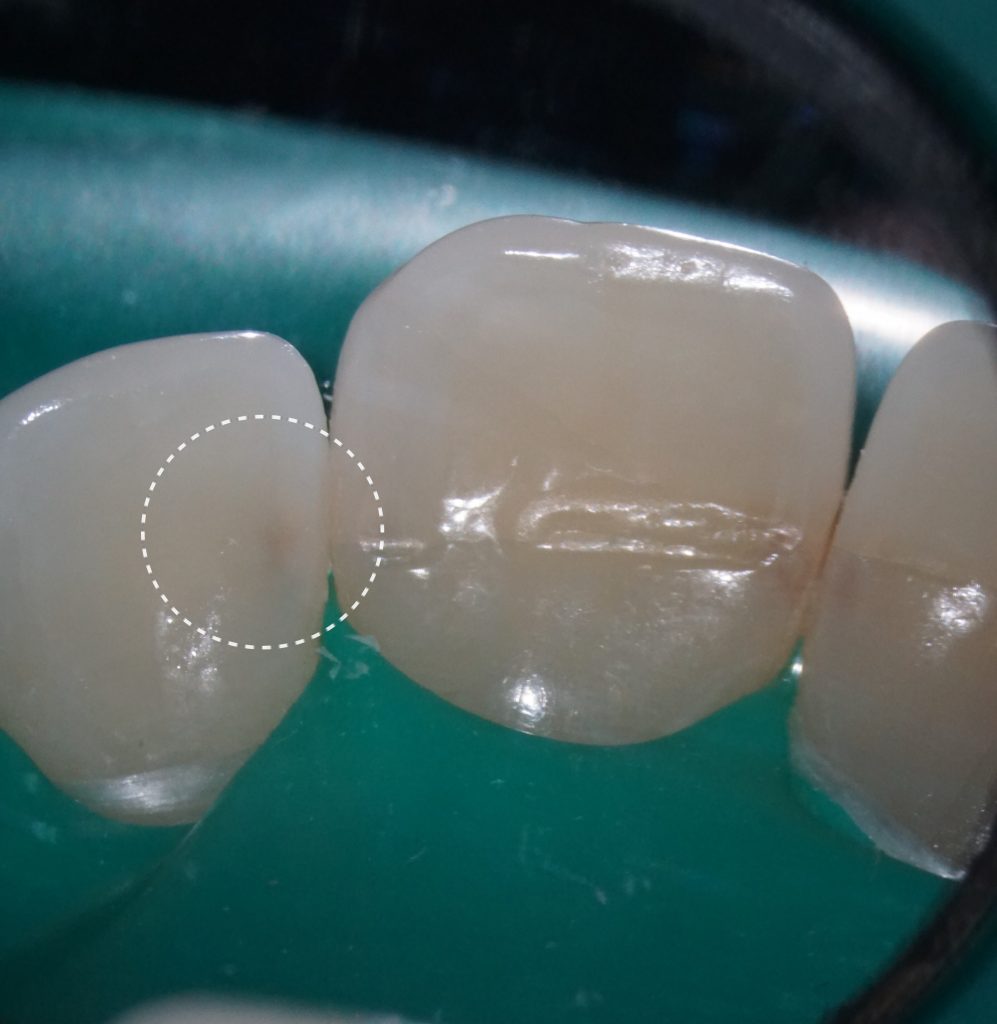

Во время клинического осмотра подтверждено наличие кариеса на мезиальной поверхности зуба 2.2